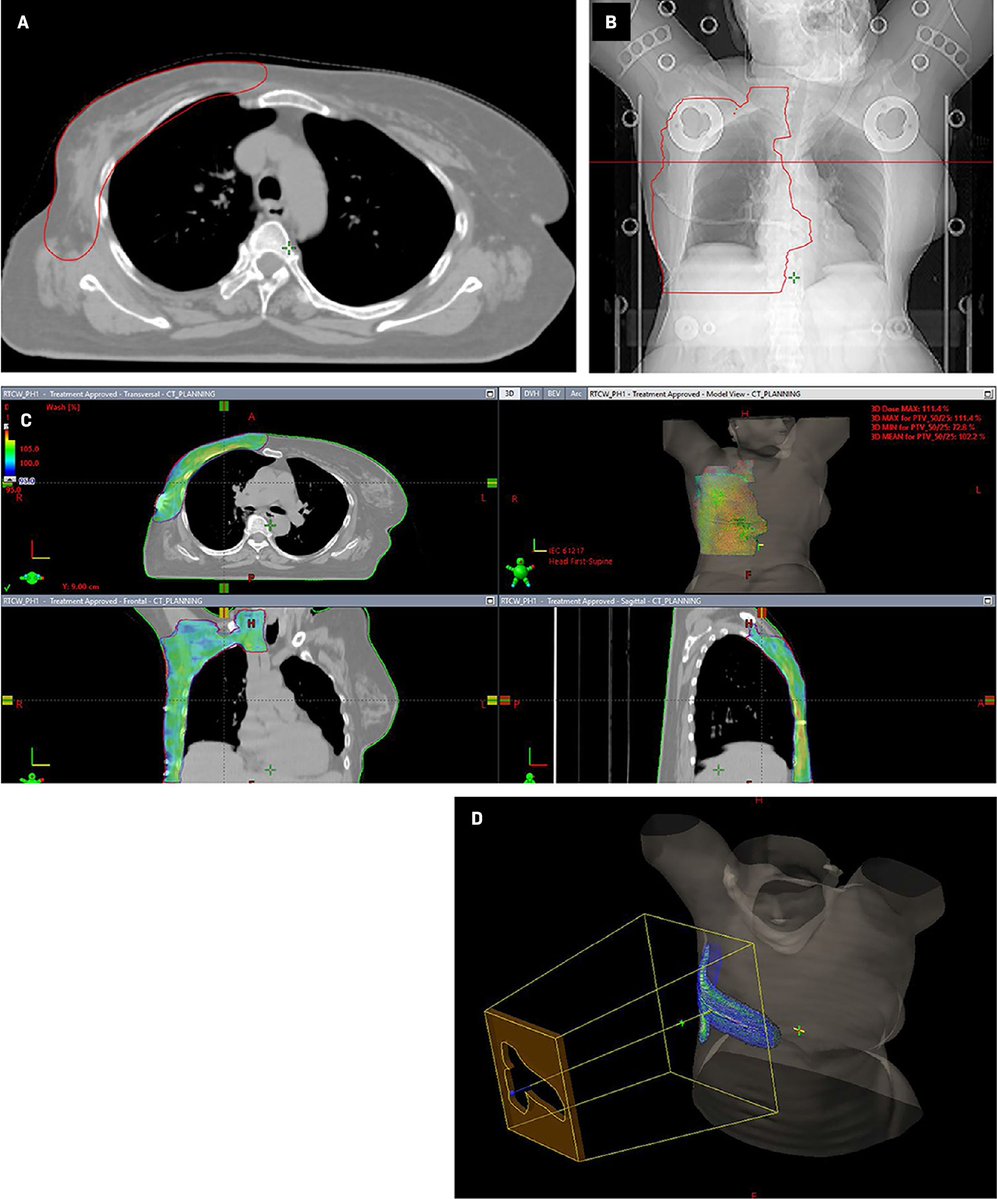

Case Report: Mediastinal Epithelioid Hemangioendothelioma in a Patient With Concurrent Early Stage Right Breast Cancer 💗🔗 ow.ly/88Kj50X8URp #BCAM25 #BreastCancerAwarenessMonth #WomensHealth #RadOncEd #MedEd